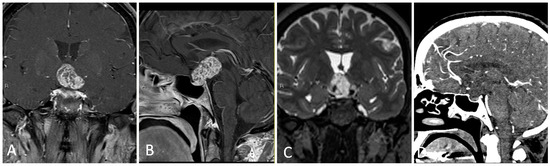

3.1.4. Illustrative Case

3.1.5. Practical Pearls

- Placement of a lumbar drain is advised at the start of surgery, or preoperatively, in cases where a high-flow CSF leak is anticipated, in order to reduce immediate postoperative intracerebral pressure (ICP) and offload excessive pressure on the skull base graft.

- Upfront harvest of a nasal septal flap may be useful for skull base reconstruction in cases of anticipated high flow CSF leak.

- The sphenoid limbus serves as an important landmark for the location of the optic nerves, bridging medial to the optic canal and forming the anterior border of the prechiasmatic sulcus.

- When approaching lesions within the suprasellar region, one should be mindful of the location of the optic apparatus (i.e., pre-fixed/post-fixed chiasm) as well as relevant neurovascular structures in the chiasmatic, lamina terminalis, interpeduncular, and prepontine cisterns.

- Craniopharyngiomas may be fenestrated into a natural CSF space, such as the basal cisterns and third ventricle, to reduce long-term cystic reaccumulation/recurrence.